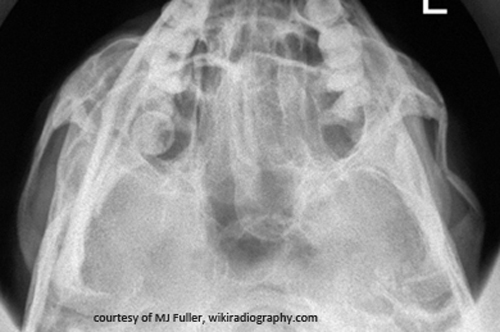

What are Jefferson fractures?